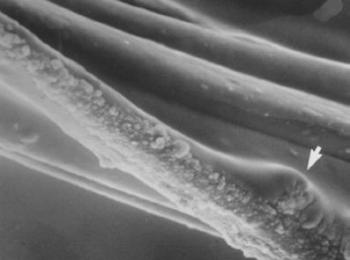

- 18. A haj és a szőrzet betegsége